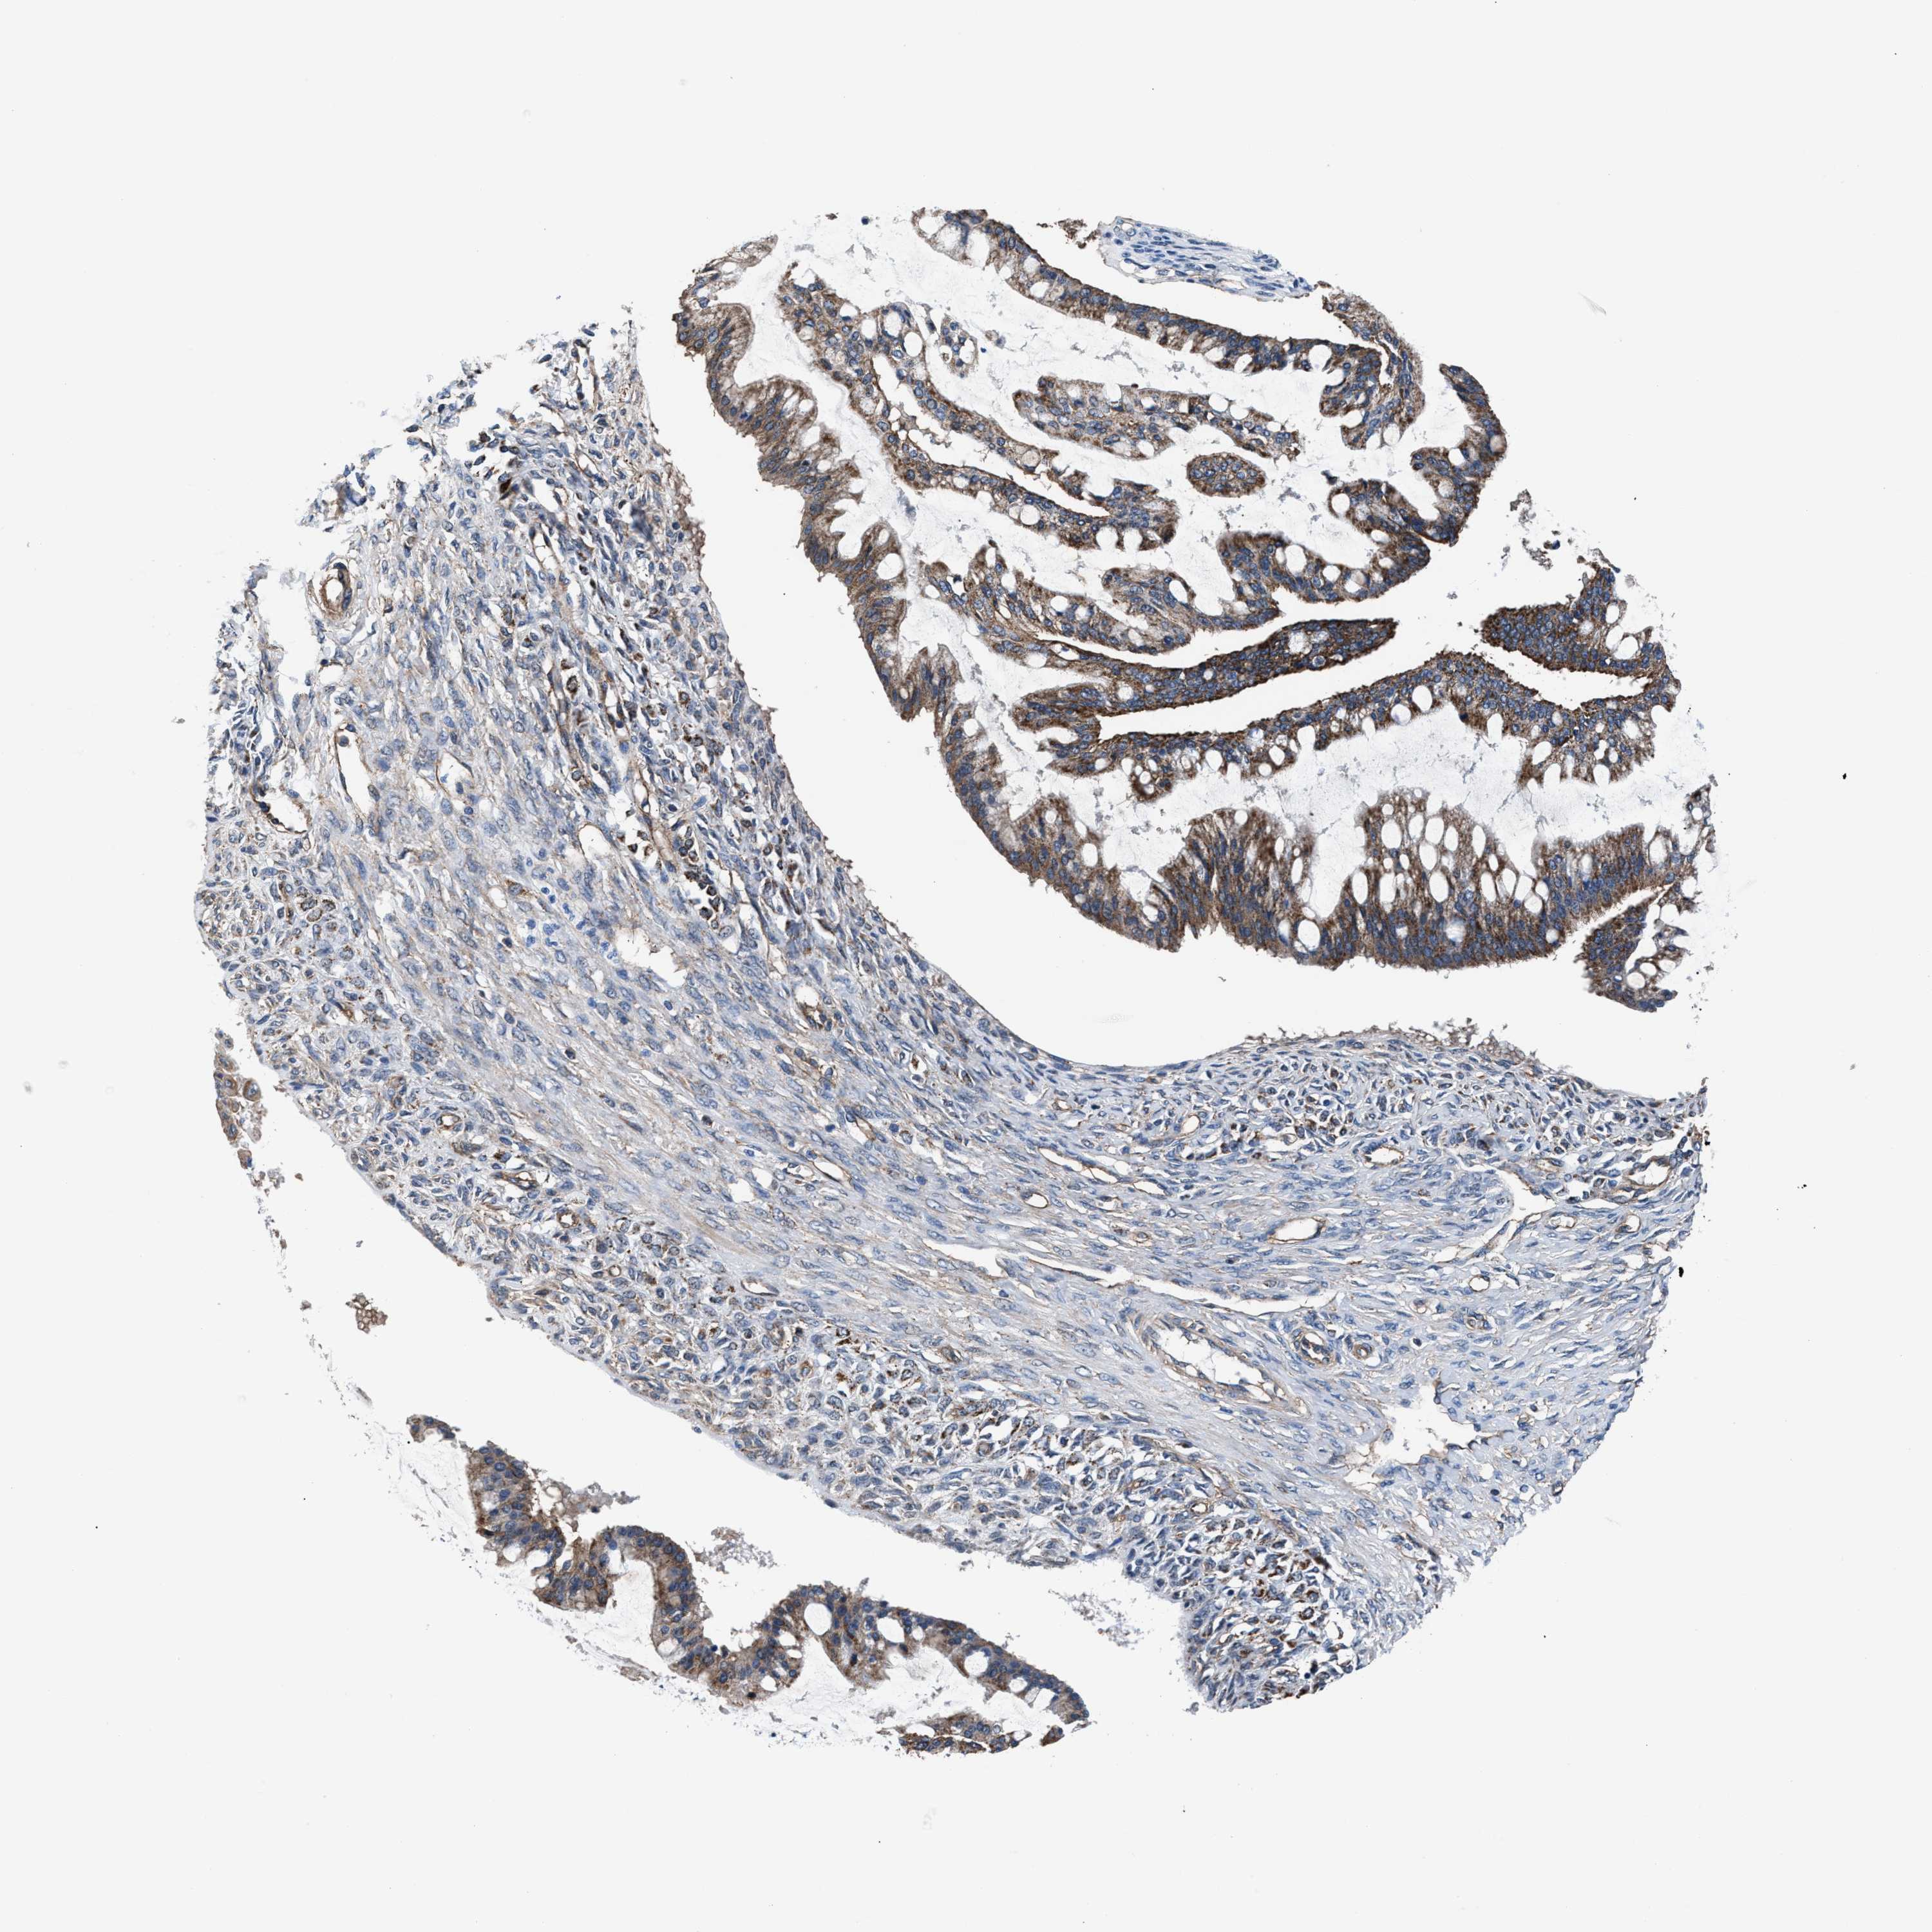

OVARIAN CANCER - Protein expressioni

A mouse-over function shows sample information and annotation data. Click on an image to view it in a full screen mode. Samples can be filtered based on level of antibody staining by selecting one or several of the following categories: high, medium, low and not detected. The assay and annotation is described here.

Note that samples used for immunohistochemistry by the Human Protein Atlas do not correspond to samples in the TCGA dataset.

Antibody stainingi

Antibody staining in the annotated cell types in the current human tissue is reported as not detected, low, medium, or high, based on conventional immunohistochemistry profiling in selected tissues. This score is based on the combination of the staining intensity and fraction of stained cells.

Each image is clickable and will lead to virtual microscopy that enables deeper exploration of all samples and also displays staining intensity scores, fraction scores and subcellular localization as well as patient and tissue information for each sample.

Antibody HPA022120

Staining

High

Medium

Low

Not detected

Intensity

Strong

Moderate

Weak

Negative

Quantity

>75%

75%-25%

<25%

None

Location

Nuclear

Cytoplasmic/membranous

Cytoplasmic/membranous,nuclear

Cystadenocarcinoma, serous, NOS

Carcinoma, endometroid

Cystadenocarcinoma, mucinous, NOS

Carcinoma, NOS